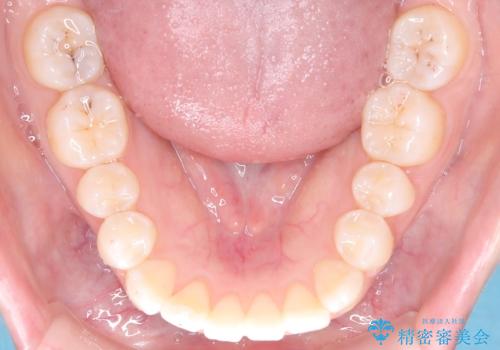

- 前歯のデコボコ(叢生)を気にされてご来院されました。精密な検査の結果、歯が並ぶスペースが不足していることが判明。患者様のご希望から、透明で目立ちにくいインビザライン(マウスピース矯正)による治療計画を立案しました。抜歯を避け、奥歯全体を奥へ動かす遠心移動という方法でスペースを確保し、前歯の叢生を解消することを目指します。

今回の矯正治療では、透明なマウスピース型の装置インビザラインを使用しました。この装置は取り外し可能で、日常生活で目立ちません。治療は、緻密に計算された計画に基づき、段階的に作製されたマウスピースを交換していくことで、奥歯から順に全体を後方へ移動させる遠心移動を実施。これにより、前歯を並べるための十分なスペースが確保され、デコボコが解消されました。抜歯することなく、機能的にも審美的にも整った美しい歯並びを獲得していただけました。